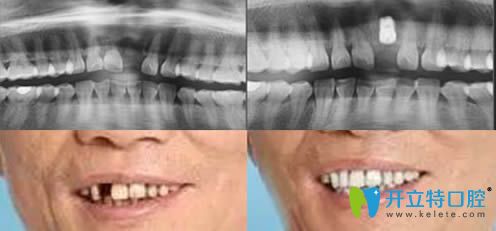

重慶皇仕口腔激光無痛美學(xué)種植牙案例效果賞析: